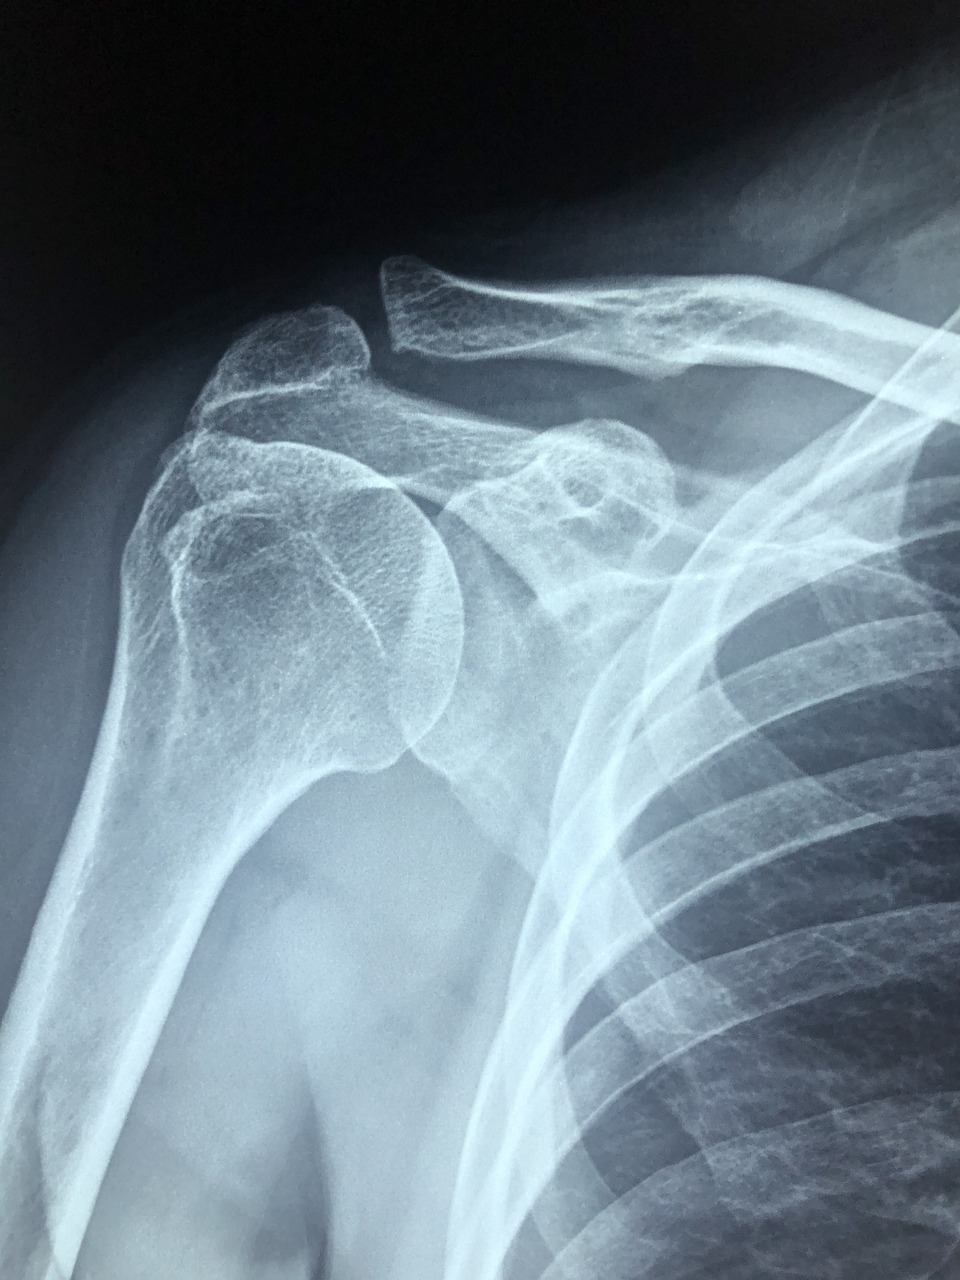

회전근개는 어깨를 감싸고 있는 네 개의 근육과 힘줄로 이루어진 구조입니다. 이 근육은 팔을 들고 움직이게 하는 중요한 역할을 하죠. 하지만 퇴행성 변화나 갑작스러운 충격으로 인해 이 회전근개가 찢어질 수 있습니다. 이것이 바로 회전근개 파열이에요.

- 정확한 진단: 초음파 또는 MRI를 통해 파열의 정도를 정확히 확인하고 치료 방향을 결정해야 합니다.